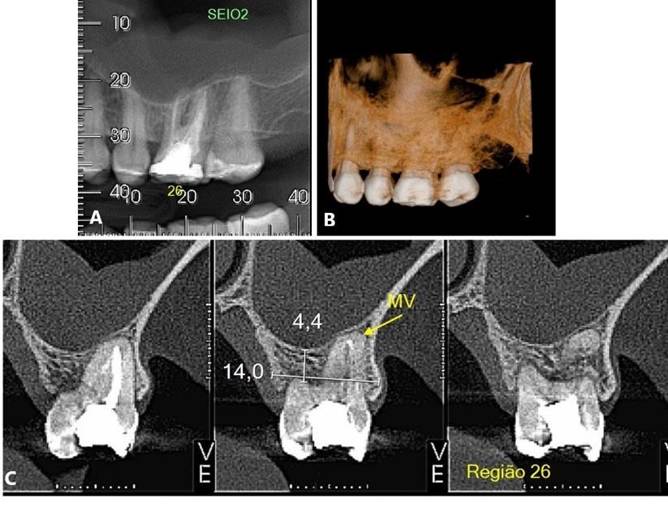

Paciente L. S. S, gênero masculino, 76 anos de idade, compareceu ao consultório particular para avaliação clínica. Durante a anamnese, paciente informou que realiza acompanhamento cardiológico e endocrinológico em virtude da hipertensão arterial e diabetes mellitus. Ao exame clínico e radiográfico (Figura 08), ausência do 26, e pouco suporte ósseo, com mobilidade excessiva, no elemento 27.

O tratamento consistiu pela exodontia do 27, instalação de implantes extracurtos ARCSYS (FGM, Joinvile – SC, Brasil) 4,3 x 5,0mm na região do 26, e implantes extracurtos ARCSYS (FGM, Joinvile – SC, Brasil) 5,0 mm x 5,0 mm no 27. A reabilitação protética foi realizada através de próteses unitárias de cerâmica. O acompanhamento está sendo realizado até o presente momento, sem alterações significativas, com resultado clínico e radiográfico satisfatório (Figura 9. A – C).

Figura 08. Radiografia panorâmica inicial

Figura 09. A, B) Radiografia periapical final. C) Radiografia panorâmica final.